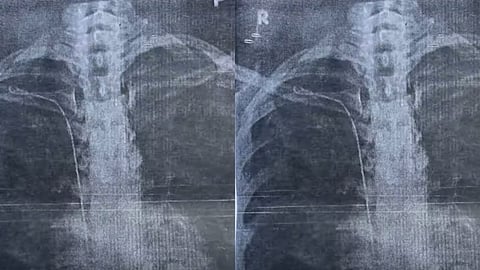

കാട്ടാക്കട കിള്ളി സ്വദേശിയായ എസ് സുമയ്യയുടെ (26) ശരീരത്തിലാണു ഗൈഡ്വയര് ഉള്ളത്.ബുധനാഴ്ച ചേര്ന്ന മെഡിക്കല് ബോര്ഡ് യോഗം എക്സ്റേ, സിടി സ്കാന് എന്നിവ പരിശോധിച്ചിരുന്നു. രണ്ടര വര്ഷം മുന്പു കുടുങ്ങിയ ഗൈഡ്വയര് എടുക്കാനാകുമെന്നാണു മെഡിക്കല് കോളജ് ആശുപത്രിയിലെ വിദഗ്ധരുടെ പ്രതീക്ഷ. ശ്രീചിത്രയിലെ ഡോക്ടര്മാരുടെ സാന്നിധ്യത്തില് ഇതേക്കുറിച്ചു വിശദമായ ചര്ച്ച നടത്തും.

ഗൈഡ്വയര് എടുക്കാമെന്നു ശ്രീചിത്രയിലെ ഡോക്ടര്മാര് കൂടി അഭിപ്രായപ്പെട്ടാല് വൈകാതെ സുമയ്യയെ സിടി സ്കാനിങ്ങിനു വിധേയയാക്കും. ആവശ്യമെങ്കില് ആന്ജിയോഗ്രാമും ചെയ്യും. ഗൈഡ്വയര് ഞരമ്പുകളില് ഒട്ടിച്ചേര്ന്നിട്ടില്ലെങ്കില് എടുക്കുന്നതിനു തടസ്സമില്ല. ചെറിയ രീതിയില് ഒട്ടിപ്പിടിച്ചിട്ടുണ്ടെങ്കിലും പുറത്തെടുക്കാന് സാധിക്കുമെന്നും മെഡിക്കല് ബോര്ഡില് അഭിപ്രായം ഉയര്ന്നിരുന്നു.

2023 മാര്ച്ച് 22നു ശസ്ത്രക്രിയയ്ക്കു വിധേയയായ സുമയ്യയുടെ നെഞ്ചില് ഗൈഡ്വയര് കുടുങ്ങിയിട്ടുണ്ടെന്ന് ഏപ്രിലിലാണു കണ്ടെത്തിയത്. ഉടന് ശ്രീചിത്രയിലെ ഡോക്ടര്മാരുടെ അഭിപ്രായം തേടിയപ്പോള് പുറത്തെടുക്കുന്നതു വെല്ലുവിളിയാകുമെന്നായിരുന്നു മറുപടി. അതിനാലാണ് അവിടത്തെ സീനിയര് ഡോക്ടര്മാരുടെ കൂടി അഭിപ്രായം തേടാന് മെഡിക്കല് ബോര്ഡ് തീരുമാനിച്ചത്.